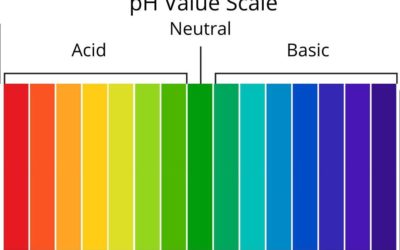

Kalzium und das Puffersystem im Blut:

Kalzium spielt im Blut nicht nur eine Rolle als Mineralstoff für Knochen, Muskeln und Nerven, sondern ist auch an der Aufrechterhaltung des Säure-Basen-Gleichgewichts beteiligt, allerdings eher indirekt als direkter Puffer. Das Puffersystem im Blut sorgt dafür, dass der pH-Wert stabil bleibt (ca. 7,35–7,45), trotz Schwankungen durch Stoffwechselprozesse oder Atmung. Kalzium interagiert hier vor allem über seine Bindung an Proteine und seine Regulation durch Hormone.

Die Verteilung dieser Formen hängt vom pH-Wert ab und wirkt sich auf die Pufferkapazität aus.

pH-Abhängigkeit: Bei einem Abfall des pH-Werts (Azidose) wird weniger Kalzium an Albumin gebunden, wodurch der Anteil des ionisierten Kalziums steigt. Umgekehrt bei Alkalose (pH-Anstieg) bindet mehr Kalzium an Proteine, und der ionisierte Anteil sinkt.